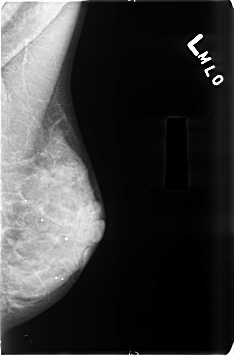

B_3496_1.LEFT_MLO

LEFT_MLO LINES 4624 PIXELS_PER_LINE 3032 BITS_PER_PIXEL 12 RESOLUTION 50 NON_OVERLAY